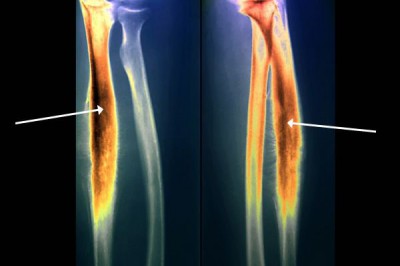

Phẫu thuật và các giai đoạn của bệnh Sarcoma Ewing

Sarcoma Ewing là một loại ung thư hiếm gặp gây ảnh hưởng đến xương hoặc mô xung quanh xương. Bệnh chủ yếu gặp ở trẻ em, thanh niên,...